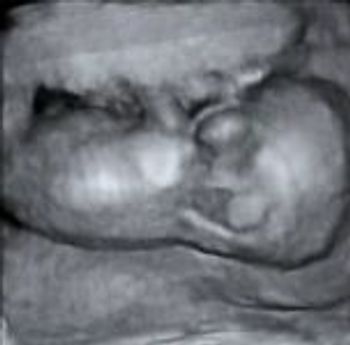

QUIZ: These images are of the jugular area in a first-trimester fetus. What do they tell you?